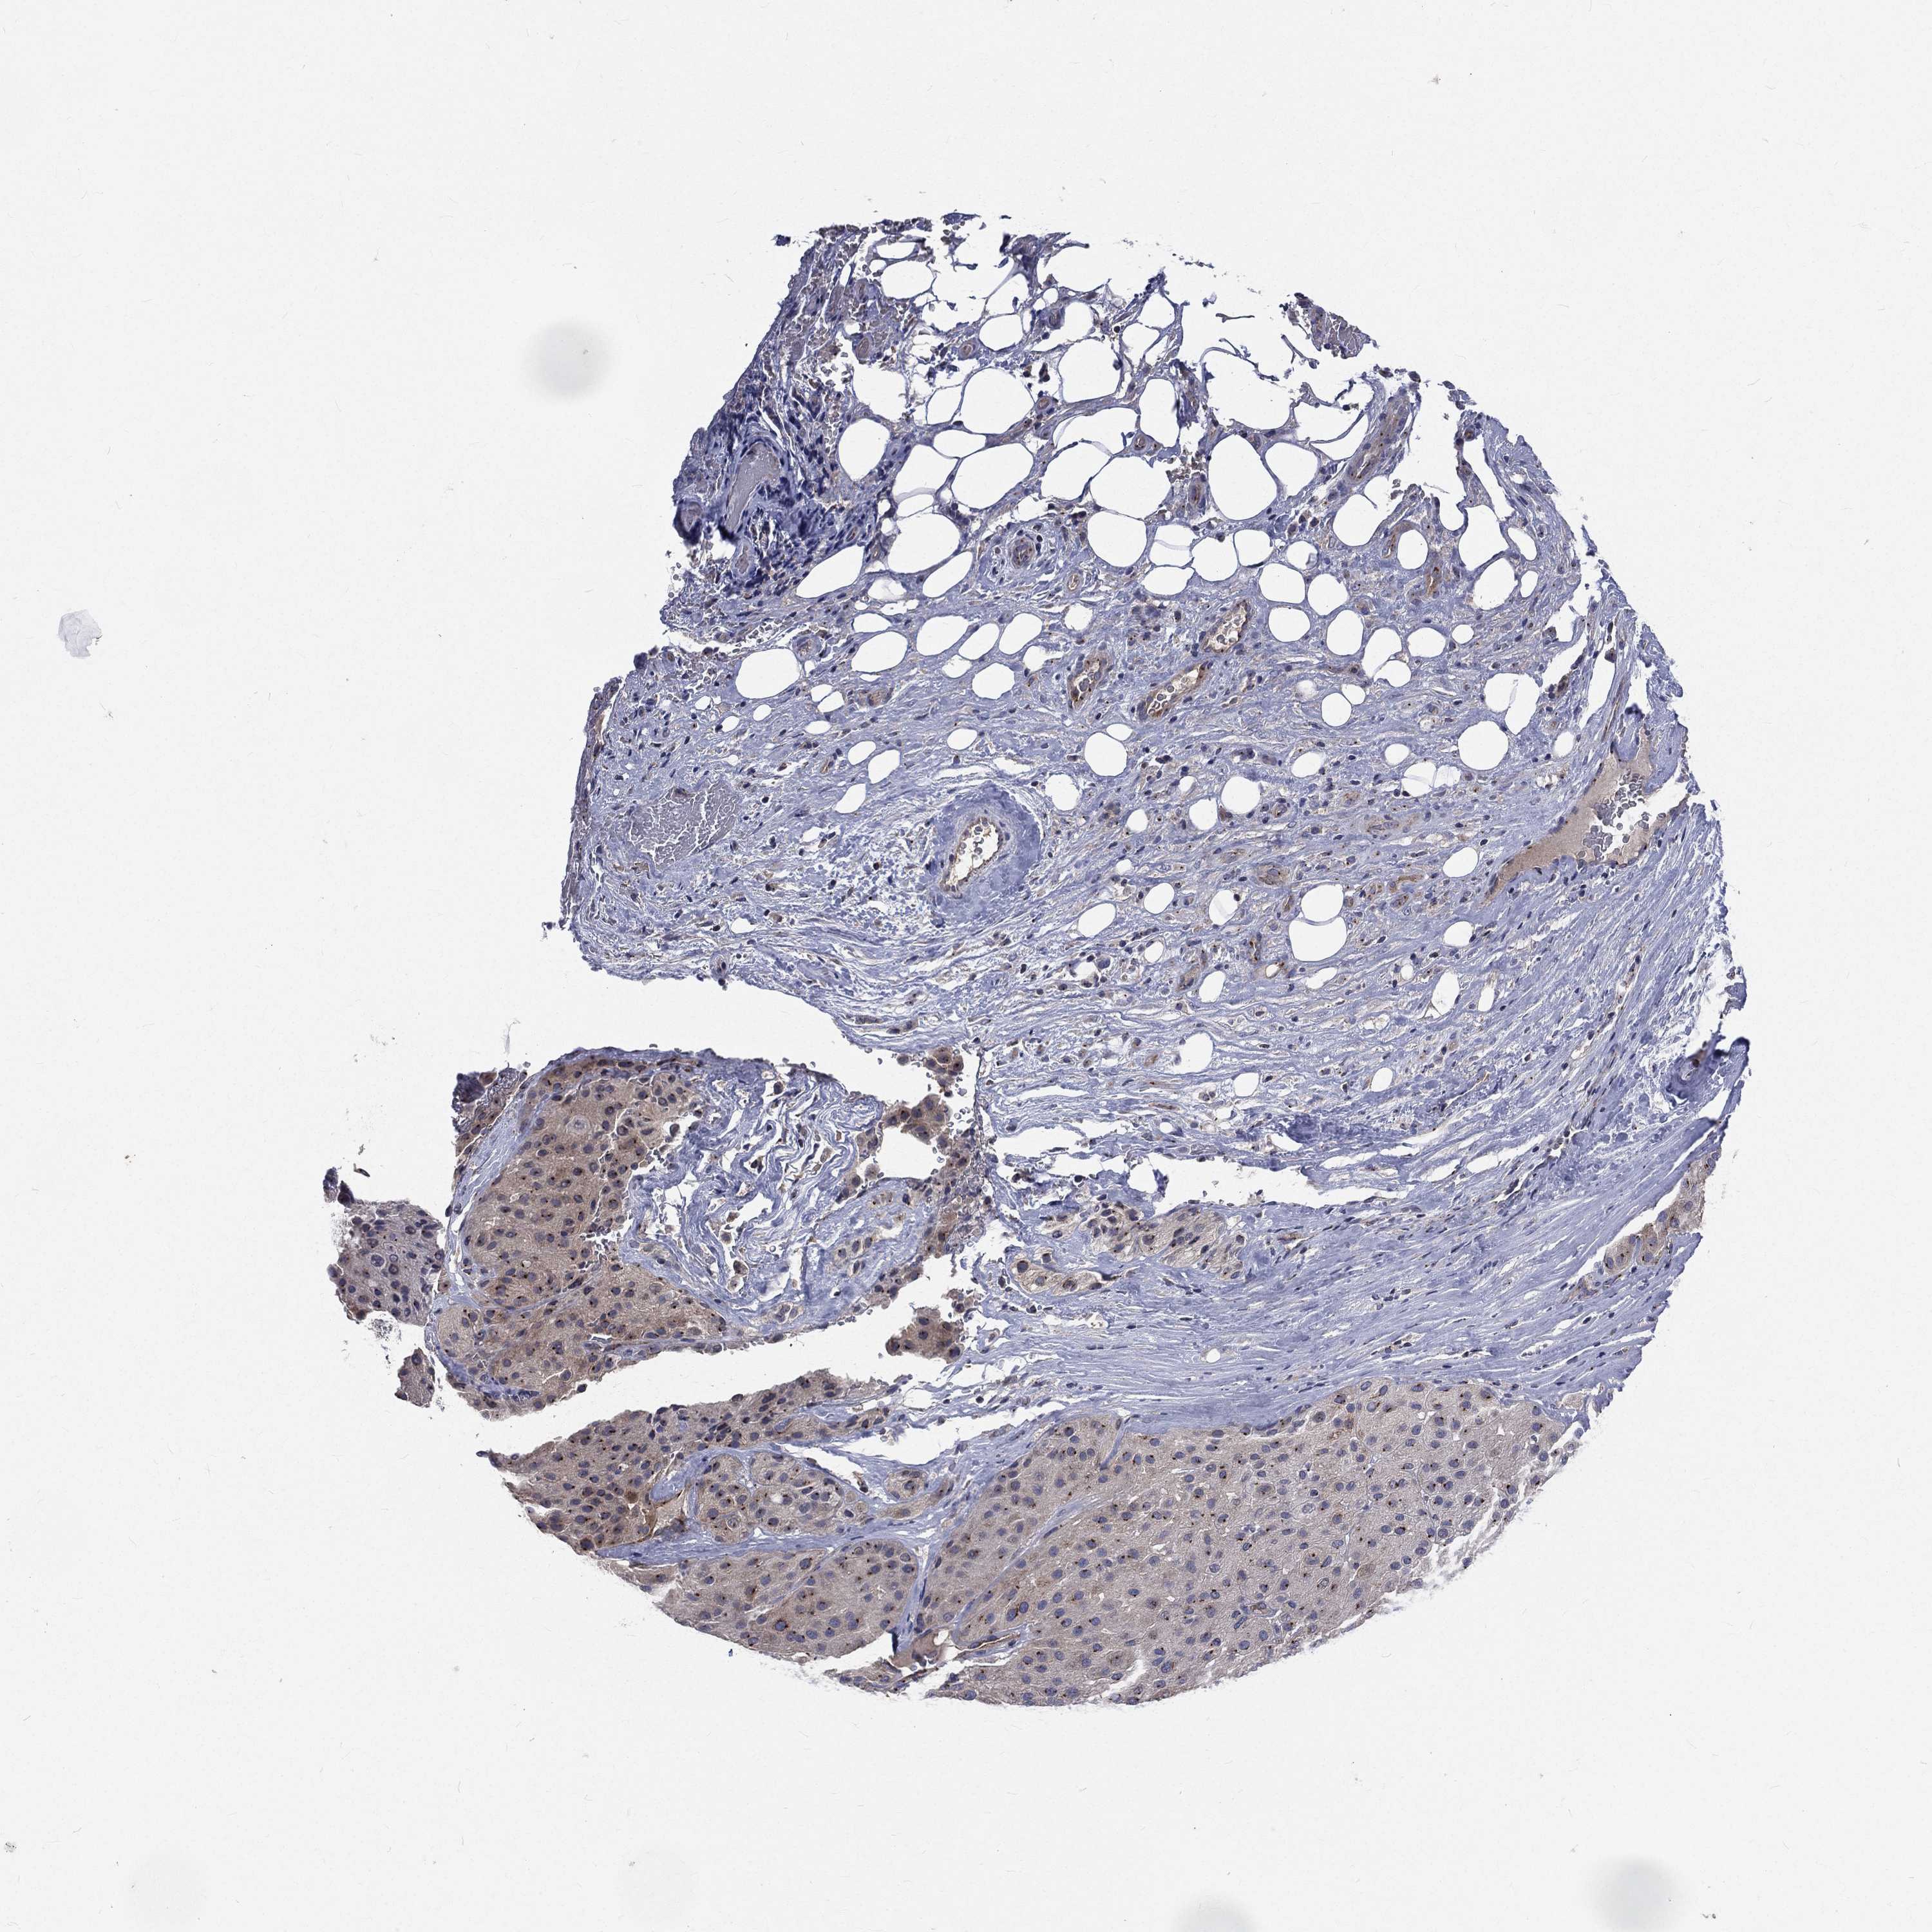

MELANOMA - Protein expressioni

A mouse-over function shows sample information and annotation data. Click on an image to view it in a full screen mode. Samples can be filtered based on level of antibody staining by selecting one or several of the following categories: high, medium, low and not detected. The assay and annotation is described here.

Note that samples used for immunohistochemistry by the Human Protein Atlas do not correspond to samples in the TCGA dataset.

Antibody stainingi

Antibody staining in the annotated cell types in the current human tissue is reported as not detected, low, medium, or high, based on conventional immunohistochemistry profiling in selected tissues. This score is based on the combination of the staining intensity and fraction of stained cells.

Each image is clickable and will lead to virtual microscopy that enables deeper exploration of all samples and also displays staining intensity scores, fraction scores and subcellular localization as well as patient and tissue information for each sample.

Antibody HPA021191

Antibody HPA021762

Malignant melanoma, NOS

Malignant melanoma, Metastatic site